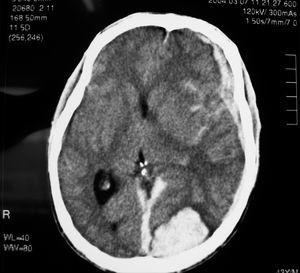

El paciente ingresó en la unidad de vigilancia intensiva de neurocirugía, donde fue valorado por el servicio de infecciosas. Por sus antecedentes, la presencia de petequias y múltiples estigmas de venopunción, y el cuadro neurológico agudo se solicitó ecocardiograma transtorácico urgente, con imagen indicativa de vegetación sobre válvula aórtica, que fue preciso confirmar con ecocardiograma transesofágico (fig. 2). Con el diagnóstico de endocarditis infecciosa se inició tratamiento parenteral con cloxacilina (2 g/4 h) y gentamicina (80 mg/8 h), sustituido a las 72 h por penicilina G sódica (4 MU/4 h) y gentamicina (80 mg/8 h) por aislamiento de Staphylococcus aureus sensible a penicilina en los hemocultivos del ingreso. En neurocirugía se decidió una actitud conservadora, por el alto riesgo quirúrgico, y no se llegó a realizar arteriografía. Una ecografía abdominal mostró esplenomegalia con imagen hipoecogénica en polo inferior sugestiva de infarto/hematoma. Tras deterioro clínico y radiológico (objetivado en una segunda TC realizada a las 72 h [fig. 3]), se produjo el fallecimiento del paciente en el cuarto día de ingreso, con el diagnóstico final de endocarditis infecciosa aórtica por S. aureus, complicada con embolismo esplénico y rotura de aneurisma micótico en el SNC como causa primera de la muerte, favorecida por coagulopatía y trombopenia multifactorial (VIH, VHC, sepsis).

Figura 3. Segunda TC craneal que muestra gran aumento del hematoma intraparenquimatoso occipital, hidrocefalia y sangre ventricular.